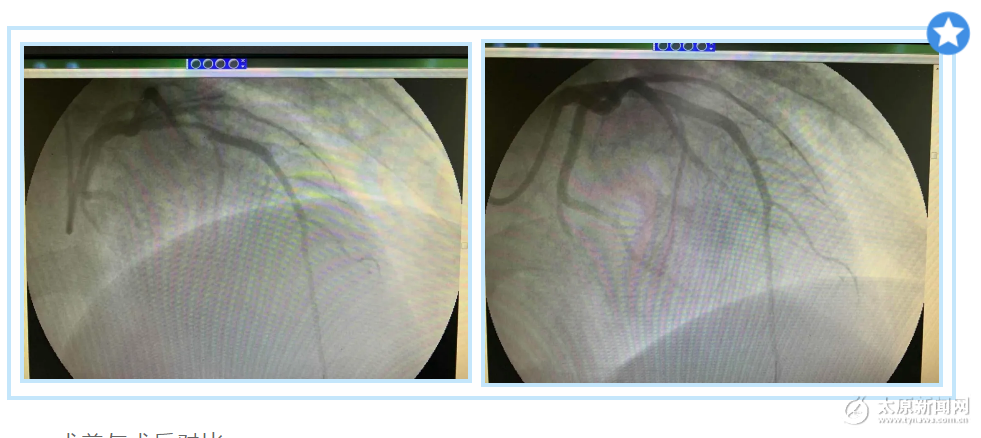

術(shù)前與術(shù)后對比

造影完畢,證實了醫(yī)生的判斷,患者的冠狀動脈血管完全閉塞了,隨后醫(yī)生通過球囊擴張將他的血管打通。至此手術(shù)結(jié)束,患者的胸痛也緩解了,病情轉(zhuǎn)危為安。目前,患者情況穩(wěn)定,心跳逐步平穩(wěn)。